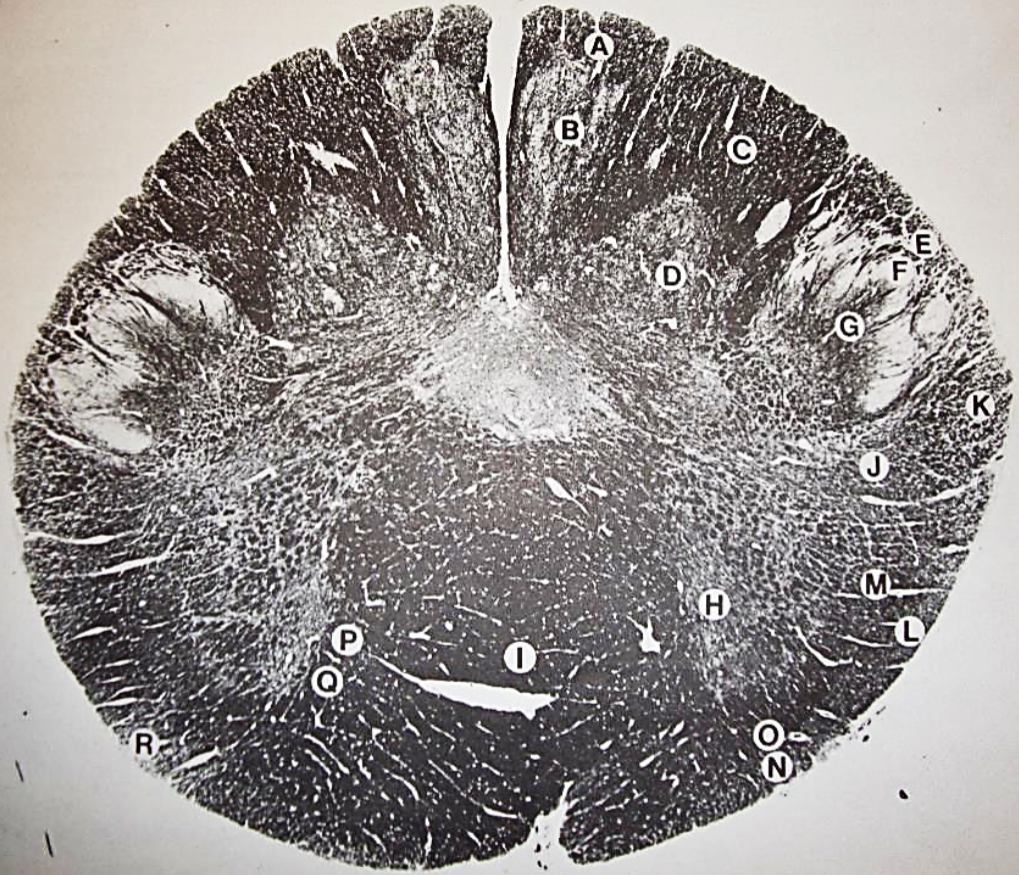

A

Lateral Cuneate nucleus

B

dorsal external arcuate fibers

C + D collectively

vestibular nuclei

C + D collectively

vestibular nuclei

E

dorsal motor nucleus of vagus nerve

F

solitary fasciculus

G

solitary nucleus

H

nucleus ambiguous

I

fascicles of glossopharyngeal nerve

J

hypoglossal nucleus

K

fascicles of hypoglossal nerve

L

dorsal longitudinal fasciculus

M

central tegmental tract

N

inferior olivary nucleus

R

inferior cerebellar peduncle

S

spinal trigeminal tract

T

spinal trigeminal nucleus

U

ventral trigeminothalamic tract

V

pyramidal (corticospinal) tract

W

rubrospinal tract

X

anterior spinocerebellar tract

Y

spinal lemniscus

Z

medial longitudinal fasciculus

a

tectospinal tract

b

medial lemniscus

c

vagus nerve

d

inferior salivatory nucleus